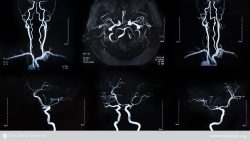

The disruption of blood flow to the brain causes a stroke and may result in an injury to the brain. The damage and recovery from a stroke can range from minimal to severe, depending on the areas of the brain that are damaged, how much of the brain is damaged, the length of time the injured parts of the brain go without blood, and how long it takes to receive treatment.

The two categories of strokes are ischemic and hemorrhagic. Ischemic strokes occur when blood clots block blood flow to an artery that supplies blood to the brain. When an artery located in the brain bursts, a hemorrhagic stroke occurs.